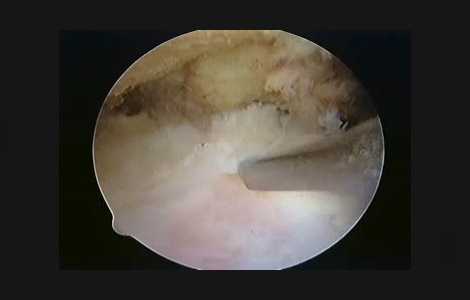

断裂していない腱板を関節鏡で滑液包側からみると

断裂した腱板を関節鏡でみると